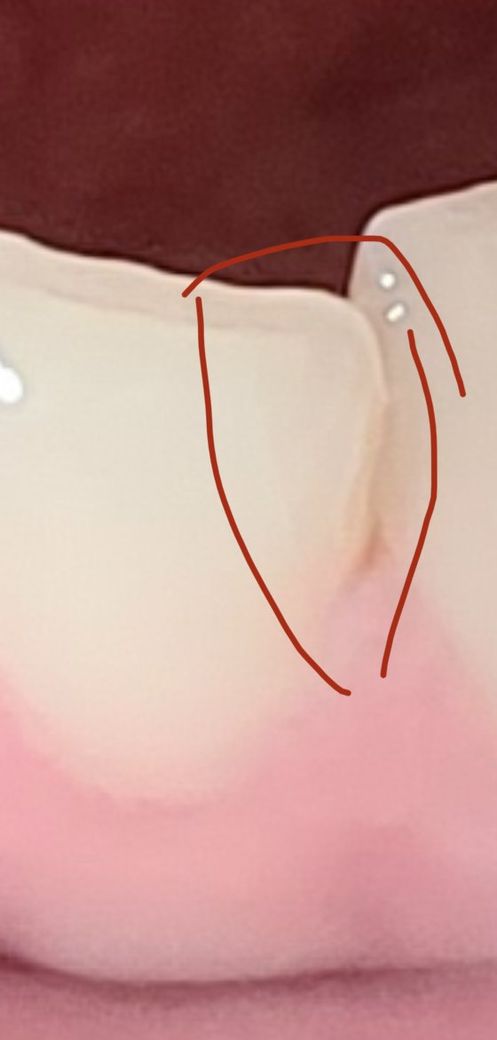

치아에 실금이 갔는데 병원에 가야할까요?

깨물다가 앞니에 실금이 갔거든요 순간적으로 따끔해서 물던걸 빼고 봤더니 아팠던 자리에 실금이 보여서요ㅠㅠ 아래에 사진 올려드립니다..ㅠㅠ 지금은 아프진않은데 혹시 계속 균열돼서 떨어져나가는거아닌지 불안해서요..

• 1번 째 사진

사진에 보이는 정도의 금은 일반적인 치아에도 나타나는 정도 입니다.

시린증상이 심하거나 통증이 있지 않다면 큰 문제가 되지는 않을것으로 보이나 정확한 확인을 위해 가까운 치과병원에서 검진을 받아보세요.

해당 사진만으로는 정확한 판단은 어려우나, 치아 측면이 살짝 깨진 것으로 보입니다.

그 외 추가적인 손상이 없는 경우에는 간단히 레진으로 떼우는 것으로 치료가 완료될 수 있습니다.

하지만 사진에 나타나지 않는 추가적인 금이 존재하는 경우에는 보철적인 치료가 필요하게 될 수도 있습니다.

깨진 치아를 방치할 경우에는 깨진 부분을 중심으로 치아가 더 심하게 깨질 수도 있고, 해당 부위에 음식이 잘 끼거나 충치가 발생하기 쉬우며 시린 증상이 나타나는 등의 불편함이 있을 수 있습니다.

사진으로 정확히 금이 얼마나 갔는지 알 수 없지만 신경이 노출될 정도로 많이 금이 간 것 같지는 않네요.

실금이 치아 표면인 법랑질에만 한정되어있다면 craze line으로 큰 문제 없을 수 있지만 내부까지 금이 가있는 것이라면 통증이 있을 수 있습니다.

저 균열이 계속되어 치아파절편이 떨어져 나갈 수 있긴하지만 치과에 가도 저부분을 떼어내고 수복하는 방법 밖에 없으므로 경과를 지켜보다가 통증이 있거나 시린증상이 있으면 가셔도 될 것 같네요.